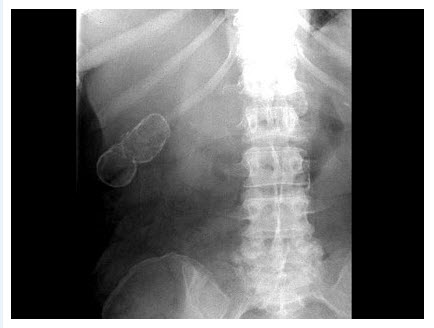

98、单项选择题

膀胱造影片见下图,你考虑什么诊断可能性大()

A.膀胱炎

B.膀胱癌

C.膀胱结石

D.膀胱息肉

E.以上都不是